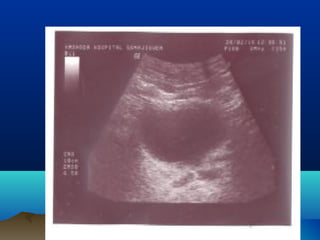

DIAGNOSISDIAGNOSIS

โ€ข ULTRASONOGRAPHY

โ€ข HYDRONEPHROSIS

โ€ข HYDROURETER โ€“ UPPER / LOWER

โ€ข CALCULI โ€“ RENAL / PUJ / URETER

โ€ข PARENCHYMAL THICKNESS

โ€ข URETERIC JET

โ€ข RENAL RESISTIVE INDEX